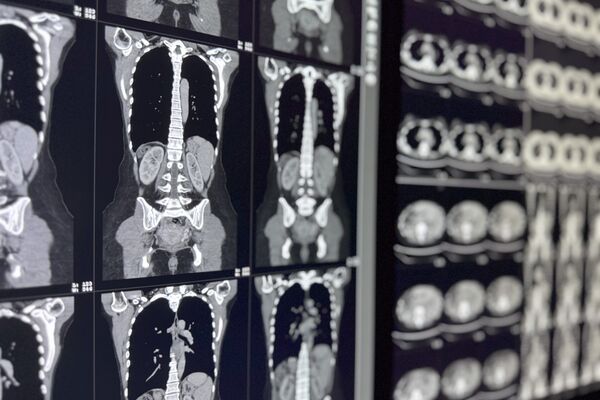

Als bildgebendes Verfahren der radiologischen Diagnostik zählt die Computertomographie zu den nicht invasiven, also nicht in den Körper eindringenden Untersuchungsmethoden.

Die zu untersuchende Körperregion wird mit einer schnell rotierenden Röntgenröhre dargestellt. Ein Computer misst dabei die Abschwächung der Röntgenstrahlen beim Durchtritt durch den Körper und ermittelt daraus in Sekundenschnelle ein aussagekräftiges, dreidimensionales Bild des zu untersuchenden Körperabschnittes. Darauf erkennen wir selbst kleinste Details, die wichtige Hinweise für die nachfolgende Behandlungsplanung liefern.

Die Computertomographie basiert auf der Darstellung von Dichteunterschieden verschiedener Gewebe. So weist z.B. Wasser eine andere Dichte als Luft oder Knochen auf, was sich im CT-Scan

in unterschiedlichen Graustufen ausdrückt. Eine noch deutlichere Differenzierung der Gewebsarten können wir dadurch erreichen, dass wir Ihnen zuvor ein jodhaltiges Kontrastmittel verabreichen.